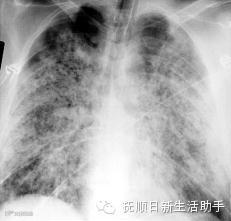

气胸

有些人,特别是老年慢阻肺患者,在用力咳嗽、剧烈运动或大笑后,会发生气胸,出现胸痛、深吸气时加剧,并放射到肩背部,严重时,还会出现呼吸困难、血压下降等紧急情况。遇到这种情况,禁忌拍背和搬动患者,以免加重气胸。应让患者取半卧位,如家中备有氧气,应立即吸氧,同时叫救护车。